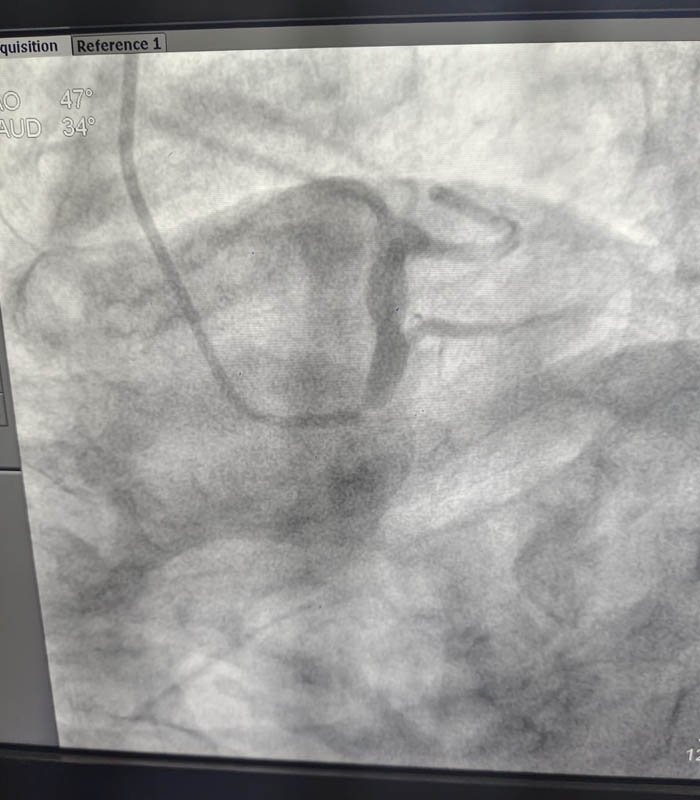

Coronary angiography (CAG) revealed a critical ostial stenosis of the left main coronary artery, a lesion known for its prognostic significance and high mortality risk if left untreated. Left main disease, especially in elderly patients, demands careful evaluation and individualized decision-making.

Technique Performed: Complex High-Risk Left Main PCI

The procedure was planned with extreme caution, focusing on safety, precision, and optimal outcomes. Key aspects of the intervention included:

• Careful lesion assessment of the left main ostium

• High-risk PCI strategy with meticulous guide catheter support

• Precise lesion preparation to ensure optimal stent expansion

• Accurate stent deployment across the critical left main lesion

• Optimization of final results to achieve excellent angiographic flow

Special attention was paid to minimizing contrast load due to the patient’s CKD, while ensuring procedural success. The intervention resulted in excellent restoration of coronary blood flow with no procedural complications